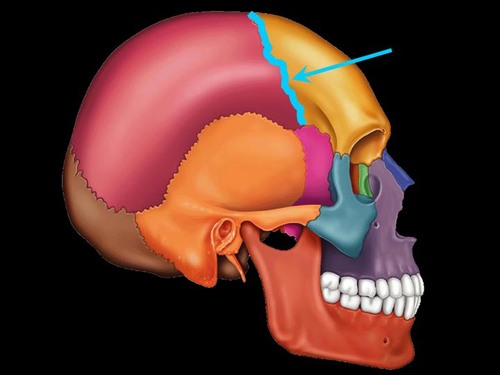

Coronal Suture

the suture between the parietal and frontal bones of the skull

Parietal Bone

either of two skull bones between the frontal and occipital bones and forming the top and sides of the cranium

Frontal Bone

bone that forms the forehead

Squamous Suture

Between parietal and temporal bones